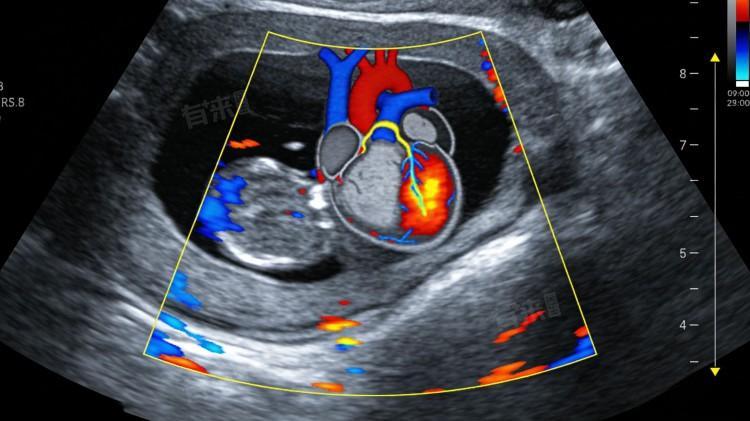

心脏彩超又称超声心动图,是一种无创、无辐射的心脏检查方法,通过超声波观察心脏的结构和功能,能清晰显示心脏各腔室、瓣膜、血管等部位的形态和运动情况,为心脏疾病的诊断、治疗和随访提供重要依据。

1、心脏腔室结构异常:心脏彩超可清晰显示左心房、左心室、右心房、右心室的大小、形态和室壁厚度,能检查出腔室扩大、室壁增厚等异常,如左心室扩大常见于高血压性心脏病、扩张型心肌病,右心室扩大常见于肺源性心脏病,室壁增厚常见于肥厚型心肌病、高血压性心脏病。

2、心脏瓣膜病变:心脏瓣膜包括二尖瓣、三尖瓣、主动脉瓣、肺动脉瓣,心脏彩超可观察瓣膜的形态、活动度和关闭情况,能检查出瓣膜狭窄、瓣膜关闭不全等病变,如二尖瓣狭窄、主动脉瓣关闭不全,还能判断瓣膜病变的严重程度,为治疗方案的制定提供依据。

3、心脏功能异常:心脏彩超可检测心脏的收缩功能和舒张功能,通过测量射血分数、舒张末期容积等指标,判断心脏泵血能力是否正常,能检查出心力衰竭,如左心衰竭、右心衰竭,还能评估心力衰竭的严重程度,监测治疗效果。

4、先天性心脏病:心脏彩超是诊断先天性心脏病的重要检查方法,能清晰显示心脏的先天性畸形,如房间隔缺损、室间隔缺损、动脉导管未闭、法洛四联症等,可明确畸形的类型、大小和位置,为先天性心脏病的早期诊断和治疗提供重要支持。

5、其他异常:心脏彩超还能检查出心脏周围的异常,如心包积液、心包增厚等,心包积液可通过彩超测量积液量,判断积液的严重程度;心包增厚常见于缩窄性心包炎;心脏肿瘤虽少见,但彩超可发现异常占位,还能观察心脏大血管形态和血流情况,排查血管异常。